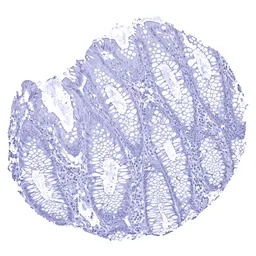

IHC-P analysis of human colon mucosa tissue section using GTX04450 UPK1B antibody [MSVA-734M] HistoMAX.

UPK1B immunostaining is absent in all cells of the colon mucosa.